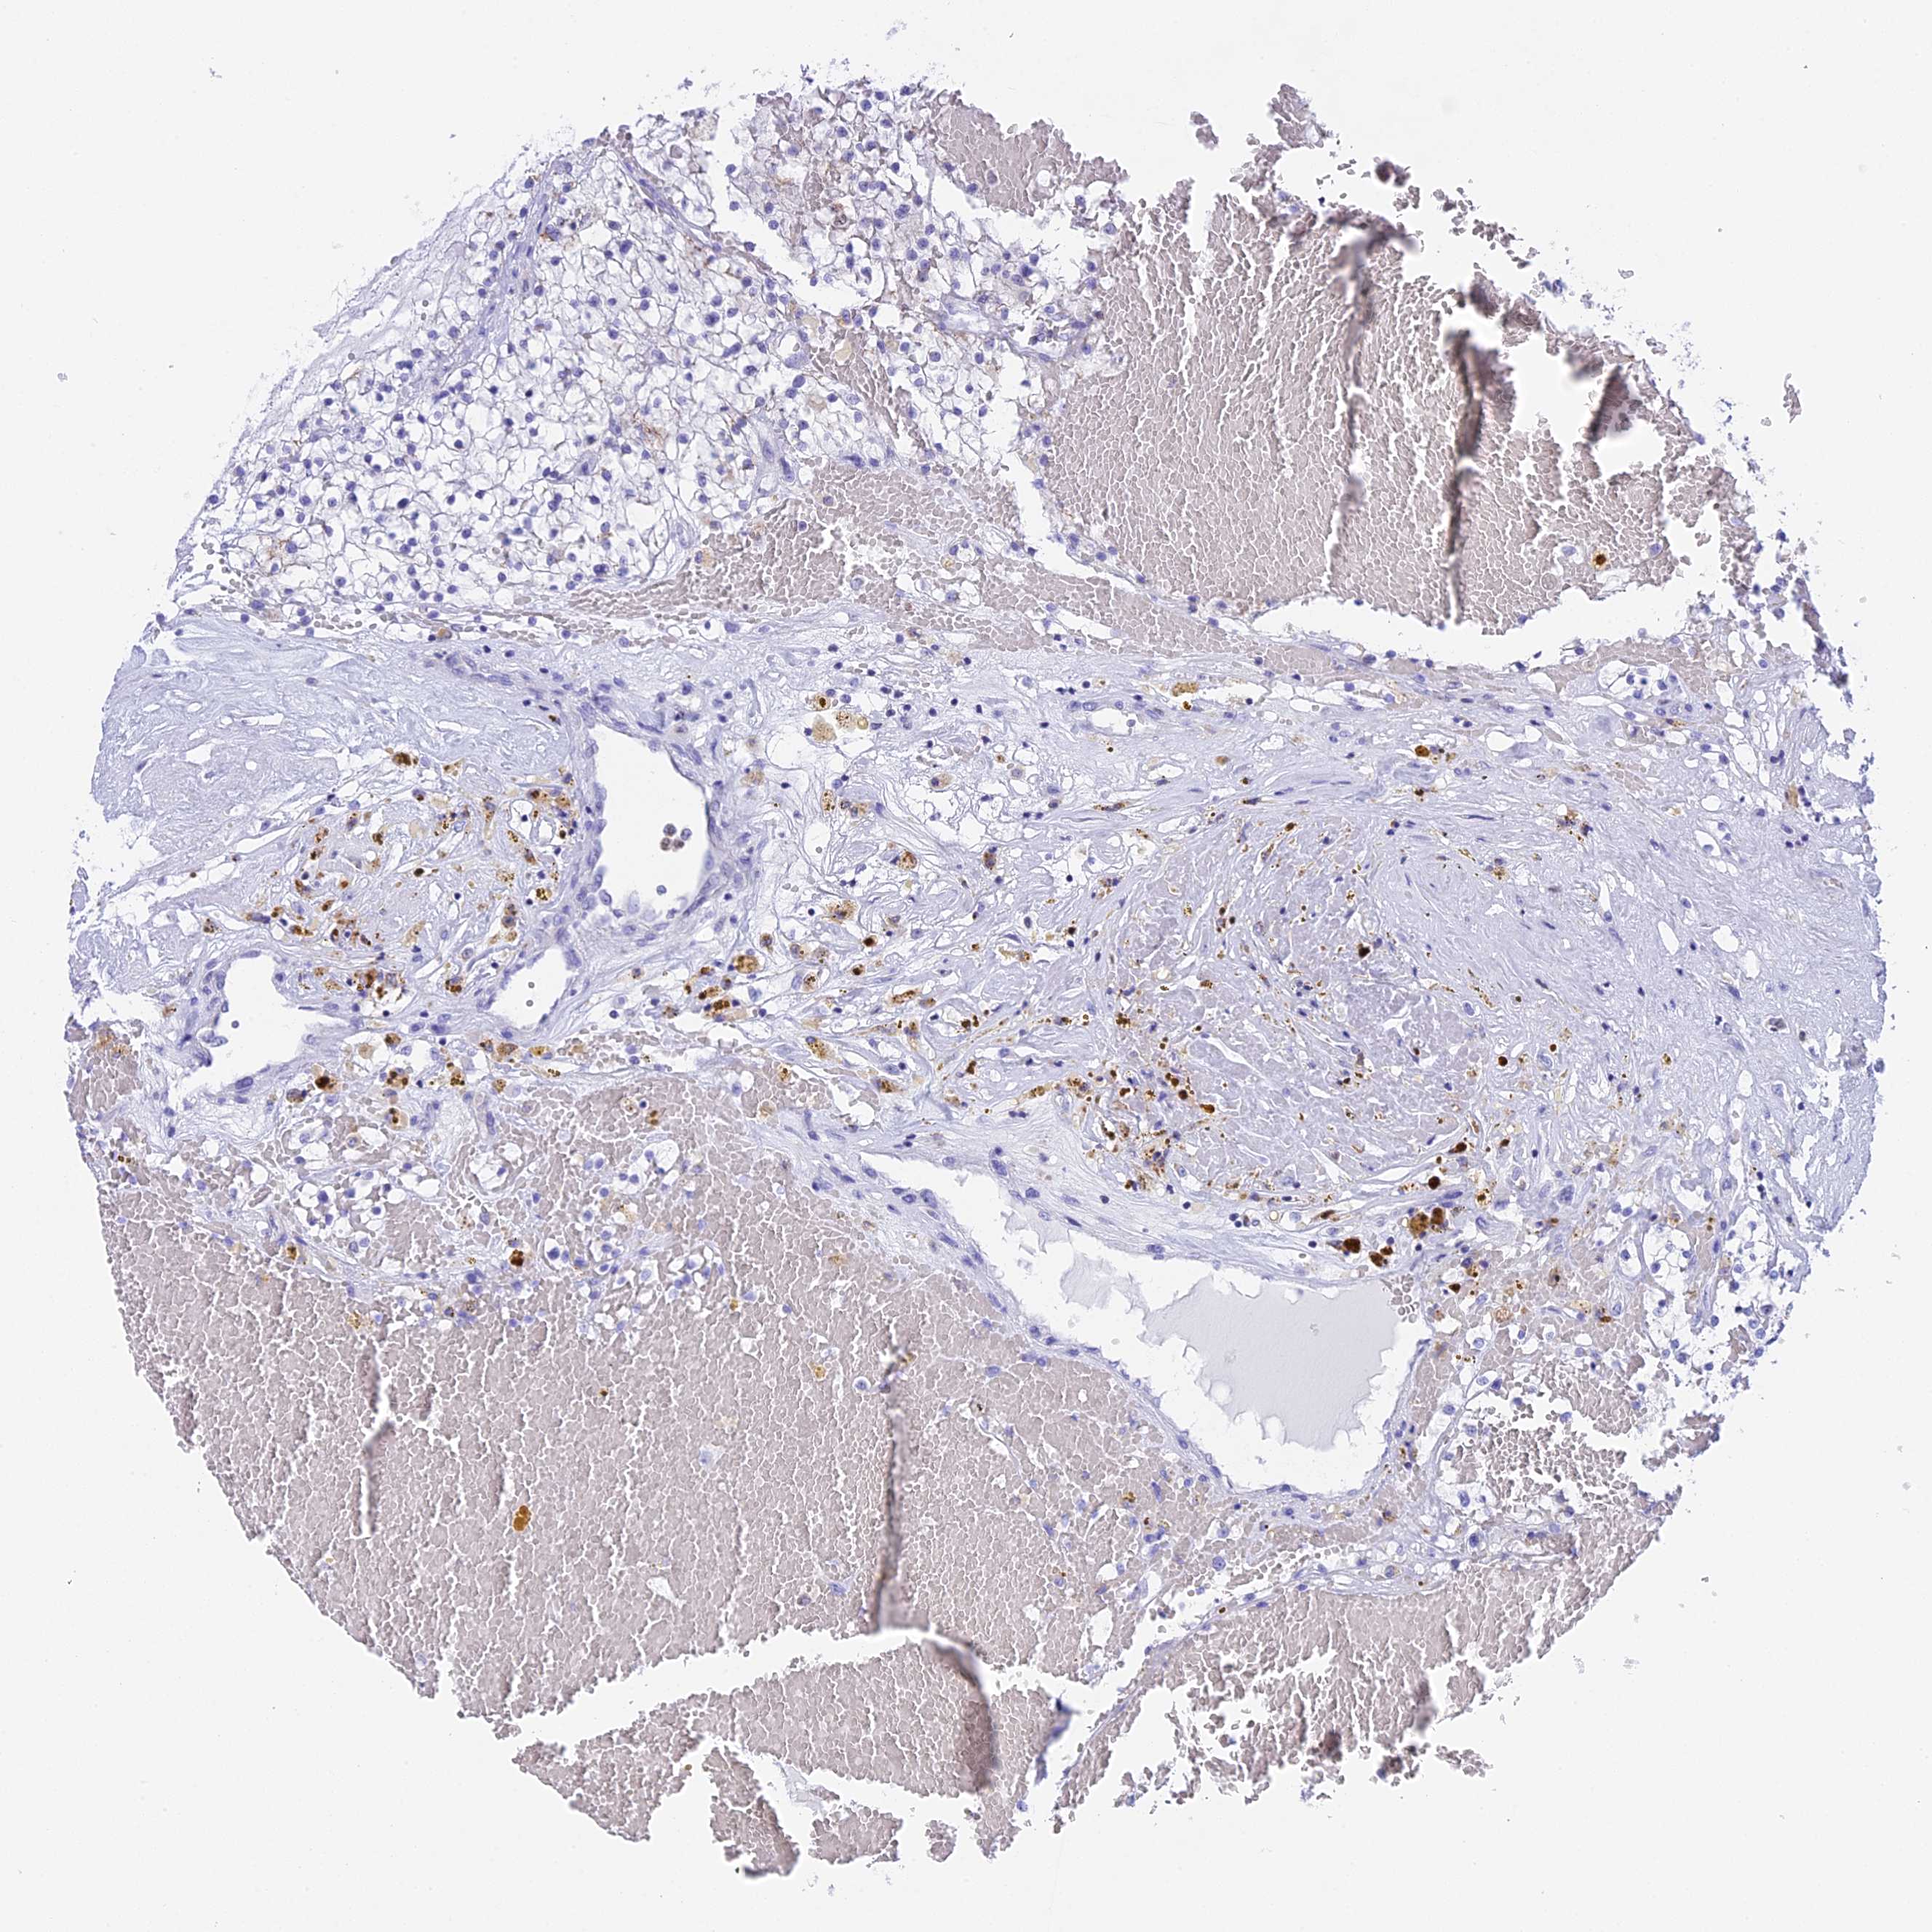

CANCER RENAL CANCER Show tissue menu

KICH TCGA KIRC TCGA KIRC VALIDATION KIRP TCGA PROTEIN RCC CPTAC PROTEIN EXPRESSION

ANTIBODIES

AND

VALIDATION